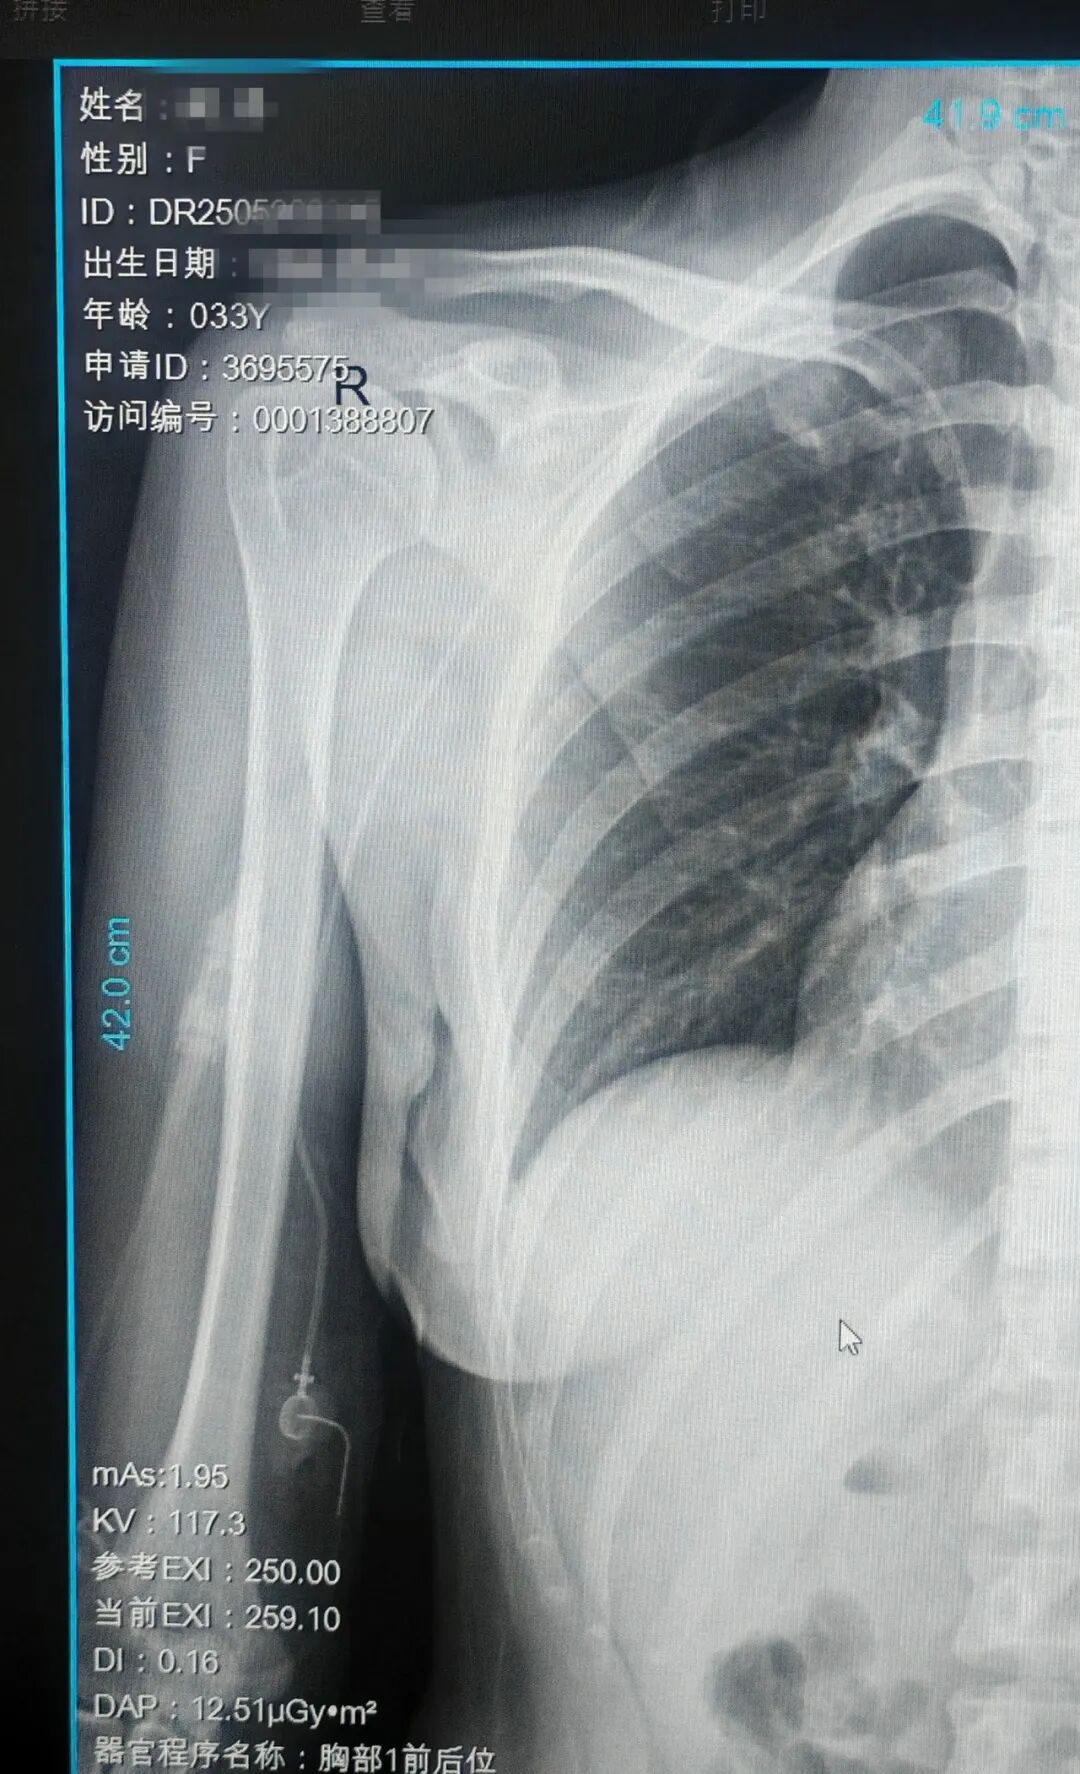

近日,晋城市人民医院门诊手术室静脉通路中心曹向枝、公卫宁护士,李鸿锐医生团队成功为一名乳腺癌术后患者实施超声联合IC-EKG(心腔内电图)定位上臂港植入术。这是我院首次开展该项技术,标志着医院在静脉治疗领域实现新突破,为肿瘤患者提供更安全、高效、舒适的静脉通路选择。

此次手术的成功实施,是我院静脉治疗团队技术实力的集中体现。曹向枝护士表示:“通过多模态技术融合,我们实现了导管定位的‘可视化’和‘精准化’,未来将进一步推广该技术,让更多肿瘤患者受益。”